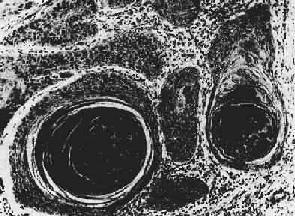

二、恶性上皮组织肿瘤由上皮发生的恶性肿瘤称为癌,多见于老年人,是人类最常见的一类恶性肿瘤。癌常以浸润性生长为主,故与周围组织分界不清。发生在皮肤、粘膜表面的癌外观上常呈息肉状、蕈伞状或菜花状,表面常有坏死及溃疡形成;发生在器官内的常为不规则的结节状,呈树根状或蟹足状向周围组织浸润,质地较硬,切面常为灰白色,较干燥。镜下,癌细胞可呈腺状、巢状或条索状排列,与间质分界清楚。亦可在间质内呈弥漫性浸润生长,与间质分界不清。网状纤维染色见癌细胞之间多无网状纤维,而只见于癌巢的周围。癌在早期一般多经淋巴道转移,到晚期才发生血道转移。 癌的常见类型有以下几种: 1.鳞状细胞癌(squamous cell carcinoma)简称鳞癌,常发生在身体原有鳞状上皮覆盖的部位,如皮肤、口腔、唇、子宫颈、阴道、食管、喉、阻茎等处。有些部位如支气管、胆囊、肾盂等处,正常时虽不由鳞状上皮覆盖,但可通过鳞状上皮化生而发生鳞状细胞癌。此癌肉眼上常呈菜花状,也可因癌组织坏死脱落而形成溃疡。癌组织也同时向深层作浸润性生长。镜下,在分化好的鳞状细胞的癌的癌巢中,细胞间还可见到细胞间桥,在癌巢的中央可出现层状的角化物,称为角化珠(keratin pearl)或癌珠(图7-12)。分化较差的鳞状细胞癌无角化珠形成,甚至也无细胞间桥,瘤细胞呈明显的异型性并见较多的核分裂像。

图7-12 鳞状细胞癌 2.基底细胞癌(basal cell carcinoma)多见于老年人面部如眼睑、颊及鼻翼等处,由该处表皮原始上皮芽或基底细胞发生。癌巢主要由浓染的基底细胞样的癌细胞构成,本癌生长缓慢,表面常形成溃疡,并可浸润破坏局部深层组织,但很少发生转移,对放射治疗很敏感,临床上呈低度恶性的经过。 3.移行上皮癌(transitional cell carcinoma)来自膀胱或肾盂等处的移行上皮,常呈乳头状,多发性,可溃破形成溃疡或广泛浸润膀胱壁。镜下,癌细胞似移行上皮,呈多层排列,异型性明显。 4.腺上皮癌 是从腺上皮发生的恶性肿瘤。根据其形态结构和分化程度,可分为分化比较好的、具有腺体结构的腺癌和低分化的、形成实体癌巢的实性癌。腺癌分泌粘液较多的则称粘液癌。 (1)腺癌(adenocarcinoma):较多见于胃肠、胆囊、子宫体等。癌细胞形成大小不等,形状不一、排列不规则的腺样结构,细胞常不规则地排列成多层,核大小不一,核分裂像多见(图7-13)。当腺癌伴有大量乳头状结构时称为乳头状腺癌;腺腔高度扩张呈囊状的腺癌称为囊腺癌;伴乳头性生长的囊腺癌称为乳头状囊腺癌。